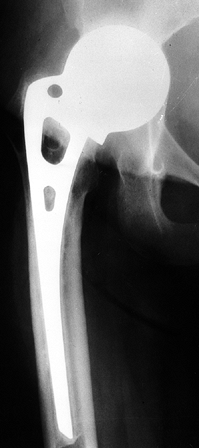

(stages I to IV-B) (Fig. 125.19). This

procedure is used in both symptomatic and asymptomatic hips, as we

found no correlation between symptoms and outcome in hips treated prior

to femoral head collapse. Results in hips with very small lesions,

especially those not in a region of major weight bearing, were

considerably better than in the group as a whole, and the question has

been raised as to how much the operative procedure adds to the outcome.

Accordingly, these patients are now given the option of nonoperative

management with close observation. Surgery is recommended, however, at

the first sign of progression.

![]() |

|

Figure 125.19. Radiographs of the left hip of an active young man with alcohol-related avascular necrosis. A: Preoperative radiographs show a large area of sclerosis and radiolucency within the femoral head. B:

Radiographs taken 1 year following core decompression and bone grafting show that the lucent areas have begun to fill in with bone. The patient remained essentially asymptomatic and was clinically doing well 12 years after the surgery. |